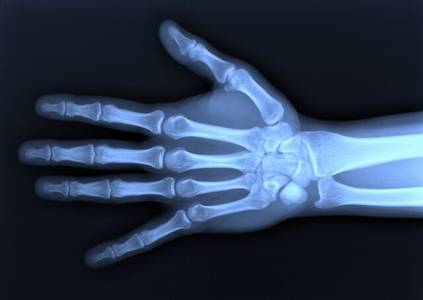

Как оказалось, икс-излучение способно проникать сквозь многие непрозрачные материалы; при этом оно не отражается и не преломляется. Рентгеновское излучение ионизирует окружающий воздух и засвечивает фотопластины. Также Рентгеном были сделаны первые снимки с помощью рентгеновского излучения.

Через короткий промежуток времени рентгеновские трубки нашли применение в медицине и различных областях техники. За это эпохальное открытие, положившее начало атомно-ядерной науке, Рентгену в 1901 году была присуждена первая в истории Нобелевская премия по физике.